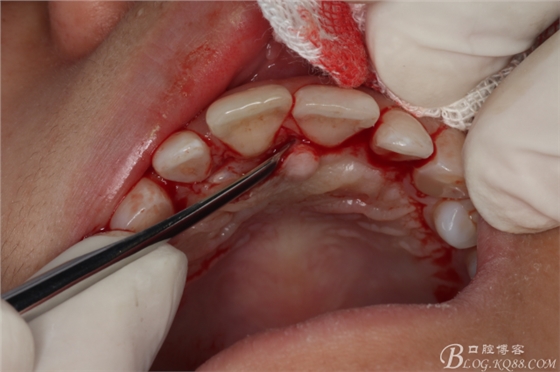

圖6.行腭側(cè)齦溝內(nèi)水平切口。

圖7.翻瓣